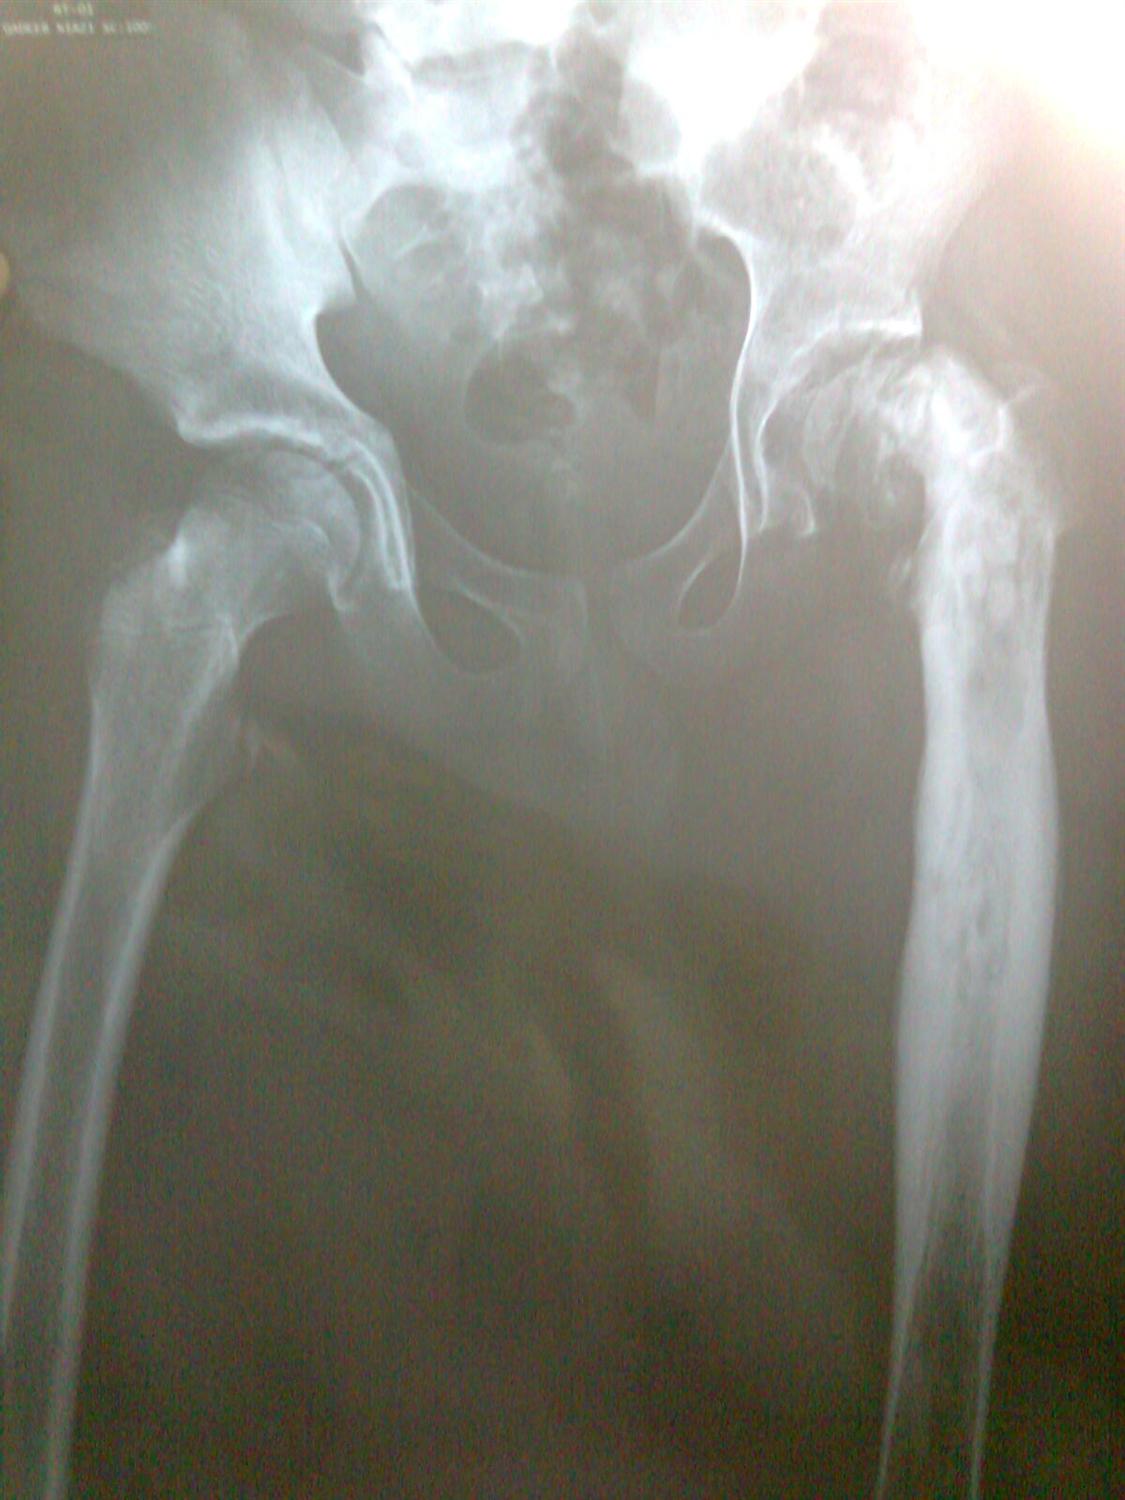

Hip Septic Arthritis Pediatric Pediatrics Septic Arthritis Treatment Orthobullets Acute septic arthritis (sa) in children is most often a hematogenous infection.1,2 the sluggish blood flow in the metaphyseal capillaries makes growing. Acutely swollen or painful joints are common complaints in the emergency department (ed). The epidemiology, microbiology, clinical manifestations, diagnosis, differential diagnosis, and treatment of septic arthritis of. While monoarticular arthritis can be due to septic arthritis, other medical. Septic Arthritis Treatment Orthobullets.